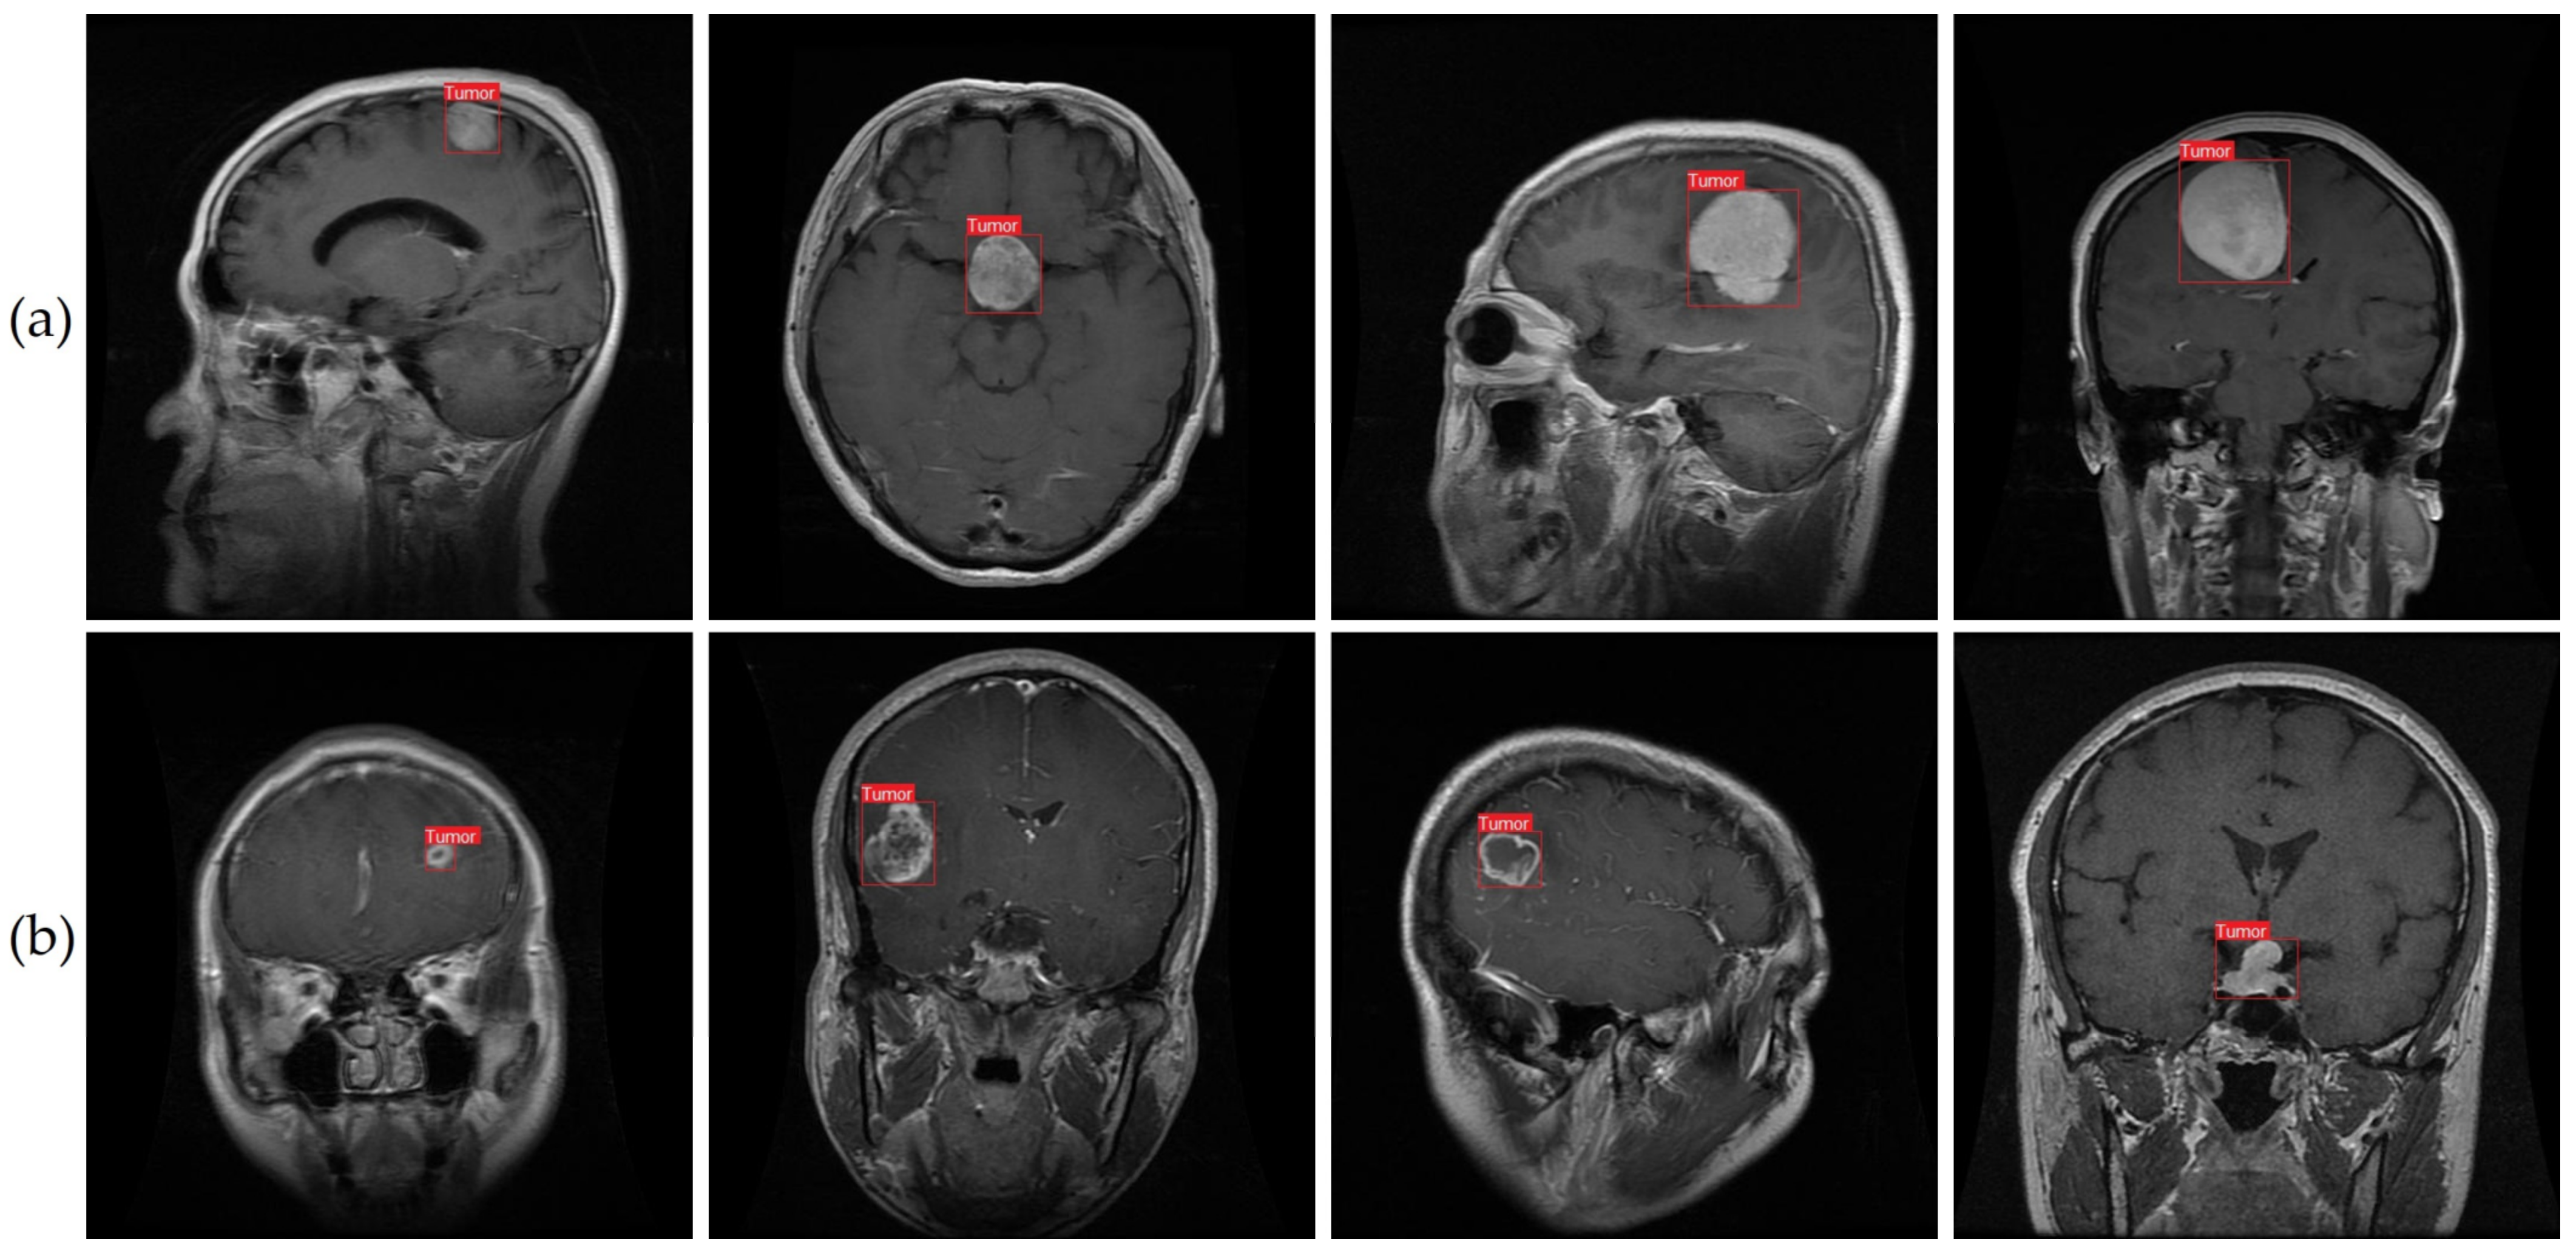

4.3. Qualitative Evaluation

We conducted qualitative research to supplement our quantitative evaluation of our suggested technique for identifying brain tumors from MRI. To do this, we selected six MRI images from our dataset. As can be seen in Figure 11, using the improved YOLOv7 model yielded consistent and trustworthy outcomes across both classes. The situations and conditions depicted in the chosen photos covered the various range of brain tumor cases. The model’s consistent execution across a variety of settings suggests that it might be useful in monitoring and detecting brain tumors using MRI.

Previous research has struggled with the correct recognition of small brain tumors in pictures. We attempted to enlarge the dataset and enhance the accuracy of tumor detection by collecting images of brain tumors of varying sizes. In Figure 11b, examples of the smaller brain tumors that were part of our dataset can be seen. We took a cue from prior work [9] and implemented a method for accurately detecting tiny objects while still retaining fine details. The method includes merging a smaller-sized feature map with a larger-scale feature map from a higher layer. The large feature map can recognize tumor pixels of various sizes using a combination of location data from lower levels and sophisticated property data from upper layers.

Figure 11 shows that our suggested method, which employs the improved YOLOv7 model, is highly successful at detecting brain cancers under a variety of conditions. Images of both large and small tumors were used to test the consistency of our method. For effective prevention and treatment of brain cancers, early diagnosis is essential [81,82,83,84,85]. Our method successfully reduces false detections while maintaining high accuracy in locating microscopic tumor areas in pictures. Our results indicate that our proposed method shows promise as a tool for facilitating diagnosis of brain tumors and enhancing patient outcomes.